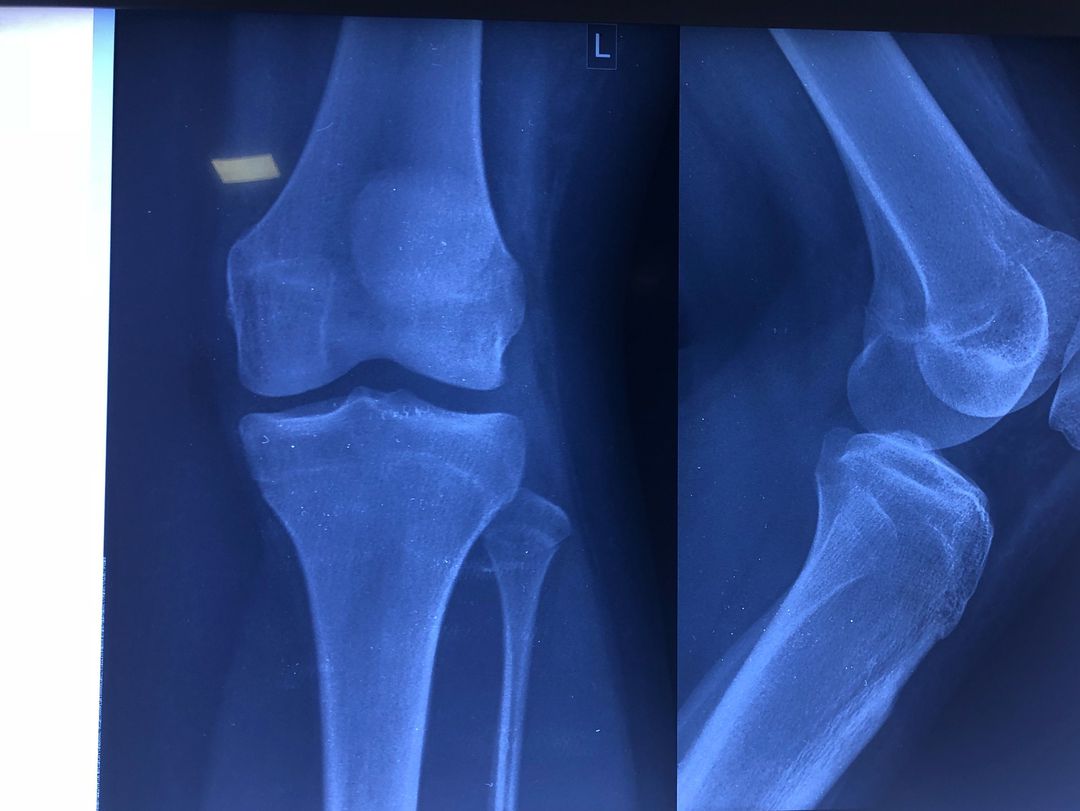

What do you see?

Orthopaedics

Fracture

Bones

Fractures